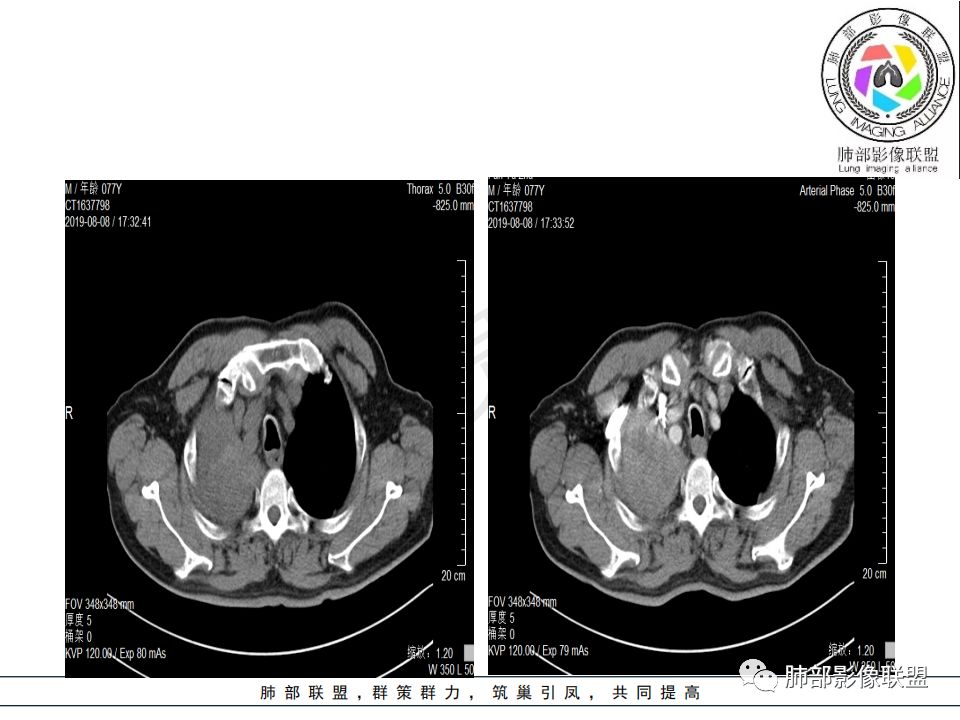

病史:男.77岁,咳嗽1月;干咳,少许白痰,无发热,2013胃癌术后,角蛋白24.65(0-3.07),SCC和proGRP不高;

影像:影像右侧大支气管阻塞,临床没有症状或很轻微,要想到胃腺癌转移;胸壁代偿好,透亮度稍低不明显,慢性过程;34.8-52.5HU,主病灶支气管前壁另有1结节,都做成增强两期了,动脉期较平扫有强化;

诊断:多发,转移,无淋巴结及胸腔积液;

晨读:患者老年男性,以咳嗽一月就诊,少量白痰,胸CT:纵隔右移,右肺体积缩小,气管下段管壁可见结节样改变,气管软骨变形,气管下段及右主支气管可见新生物向管壁浸润,并向管腔外生长,右上肺肺不张,但不张边缘可见病灶呈膨胀性生长,可见分叶,增强后强化明显。考虑:肺部恶性病变(鳞癌?)

晨读病例:老年男性,症状轻,右侧胸廓略塌陷,右肺主支气管内外软组织影,支气管变窄截断,右肺上叶不张,其内见细砂样钙化,周围看见小结节,右肺门看见一淋巴结稍大,增强不均匀强化,胃癌病史,常规考虑:转移,或原发肺恶性鳞癌。鉴别支气管TB?